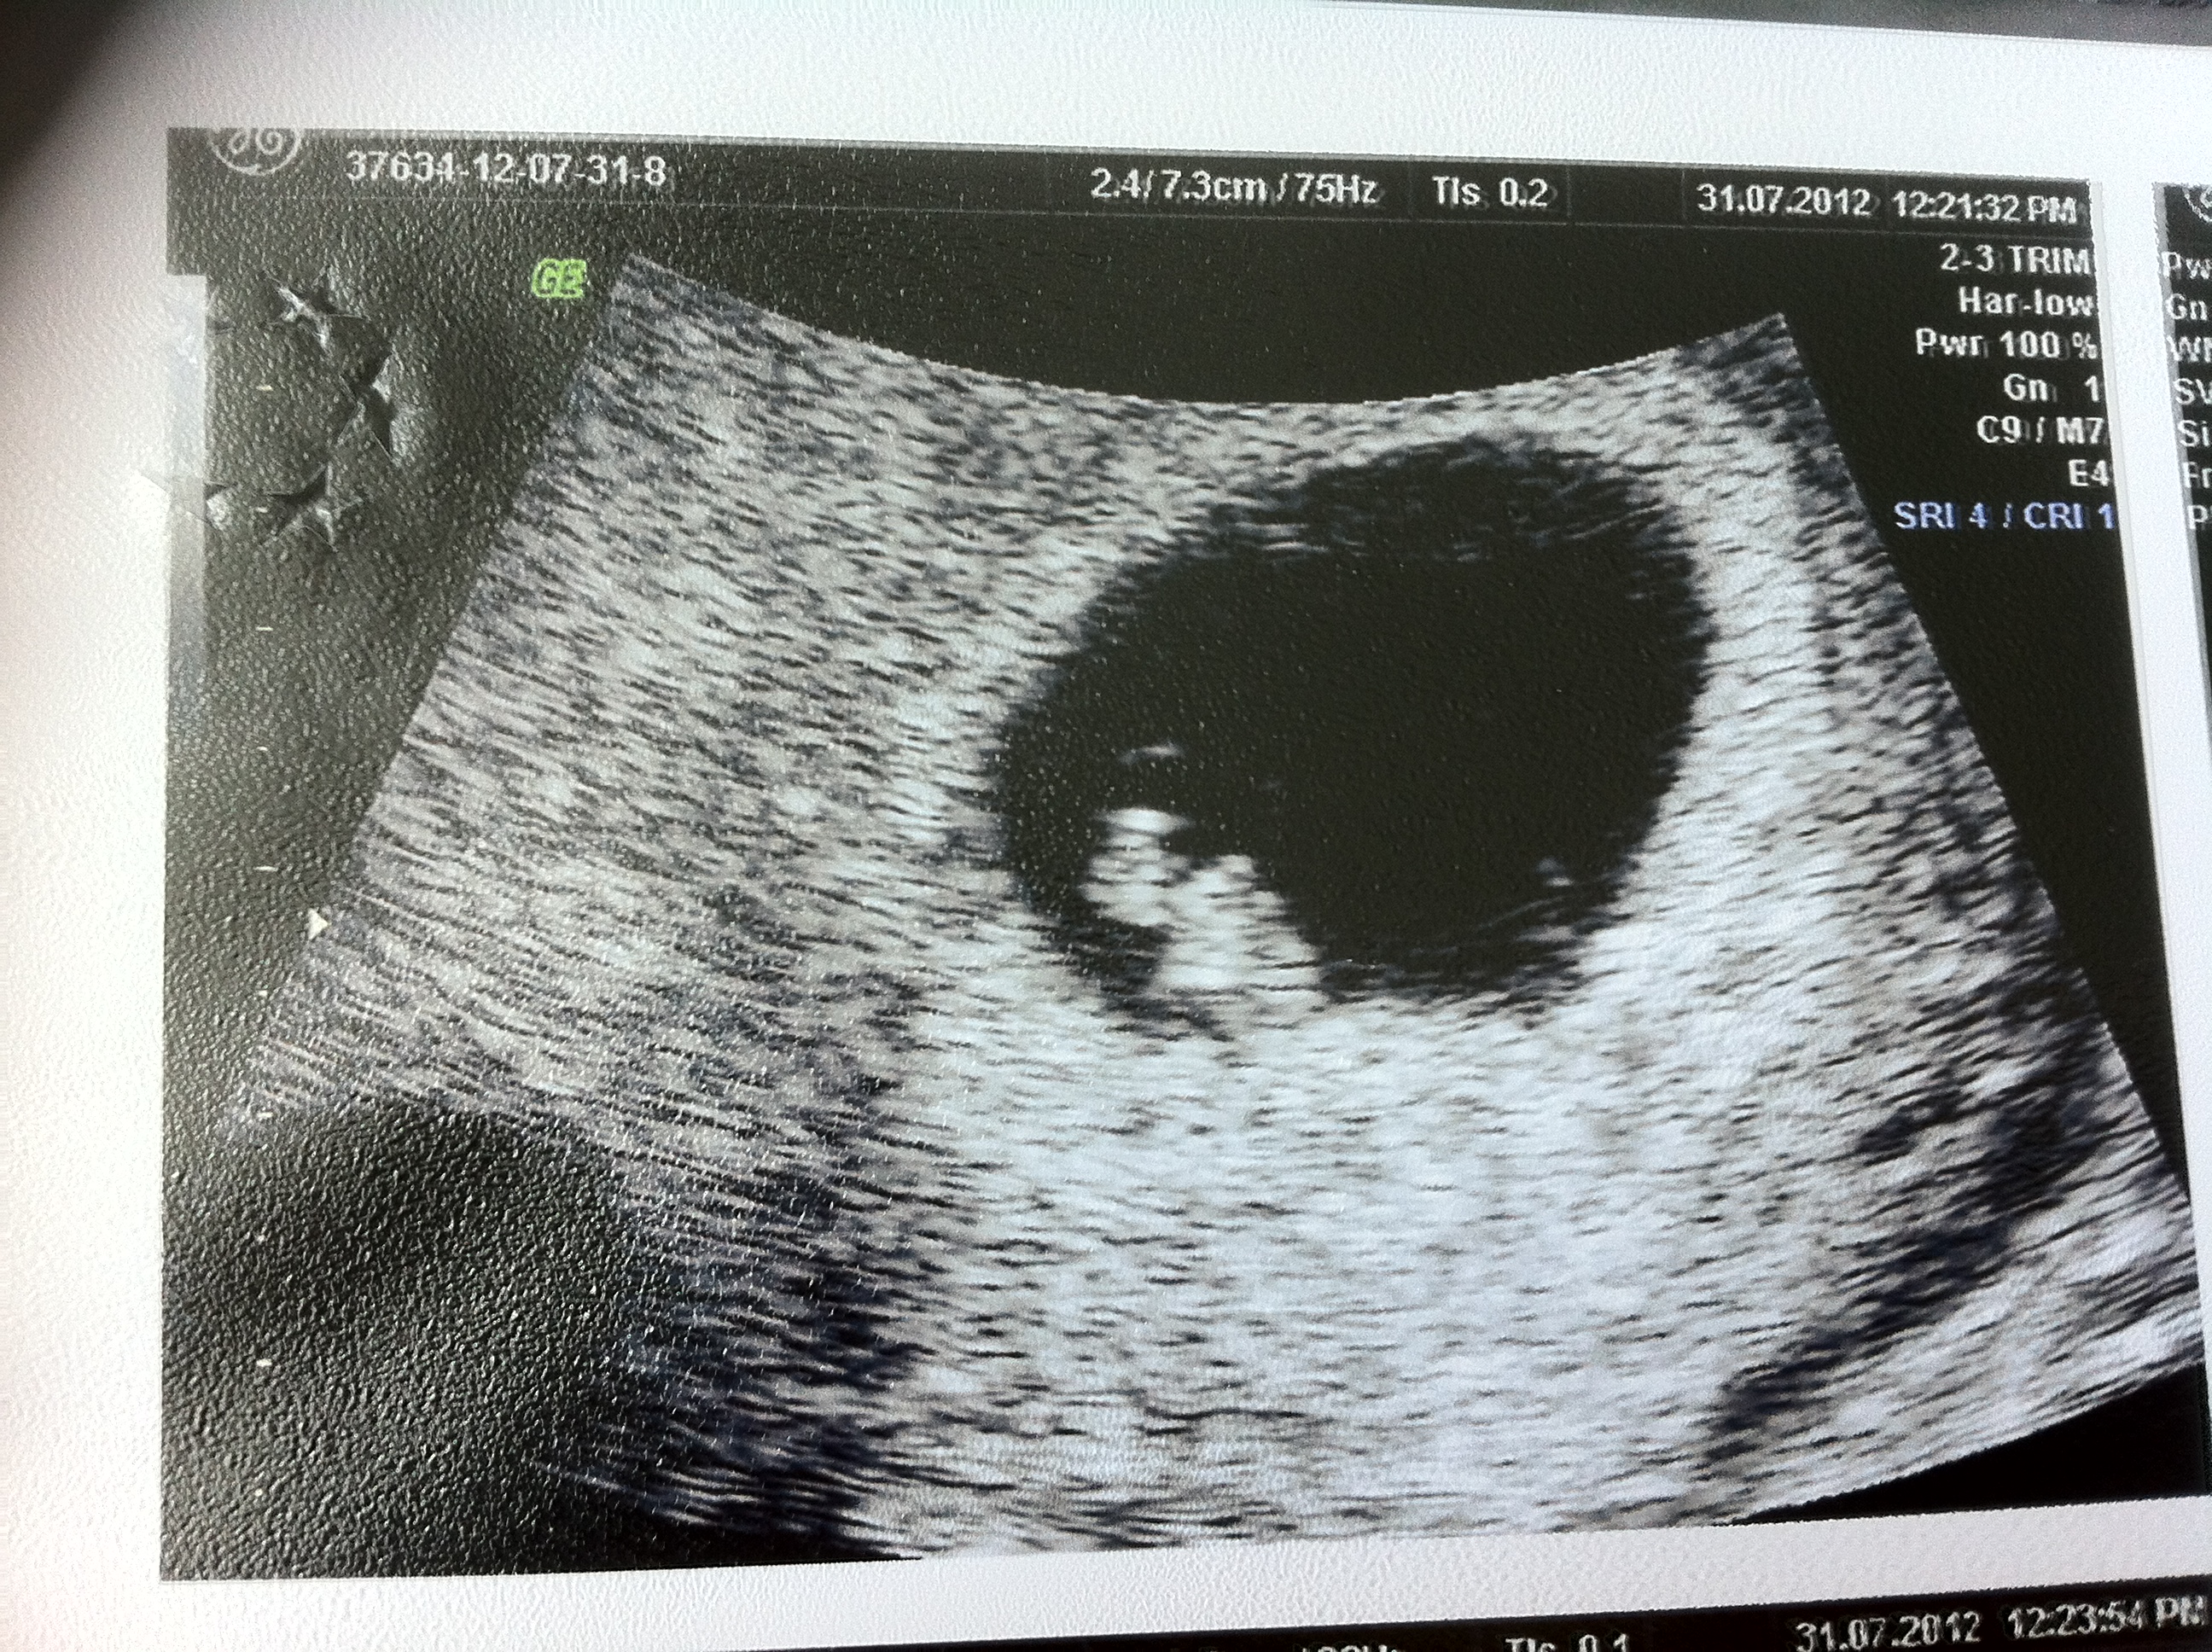

During week 10 of pregnancy, baby is as big as a strawberry, measuring about 1.2 inches long and weighing about.14 ounces. Placenta previa is more common early in pregnancy and might resolve as the uterus grows. At as early as 10 weeks, the placenta can be picked up on an ultrasound. The most exciting development this week is that your baby's heart is fully formed and beating at 180 beats per minute (double the speed of your own!) and his placenta reaches full development. Your uterus should be at the level of your belly button. A fetus that's 20 weeks along would be nurtured by a placenta about 20 millimeters thick. Placenta abruption could result in an emergency situation requiring early delivery. My placenta seemed to weigh nearly as much as my 11lb baby. Below, one mum gets a grip on what's really going on inside at week 10. I was shocked at how big it was. 19 years experience family medicine. The baby weighs about 10 ounces and is a little more than 6 inches long. The placenta is the tissue that grows inside the uterus and connects to a developing baby.

Below, one mum gets a grip on what's really going on inside at week 10. In most women, growth slows in the third trimester as your baby maxes out the space in the womb. By 18 to 20 weeks, the placenta weighs about 5 ounces. More images for how big is a placenta at 10 weeks » The most exciting development this week is that your baby's heart is fully formed and beating at 180 beats per minute (double the speed of your own!) and his placenta reaches full development. Placenta previa is more common early in pregnancy and might resolve as the uterus grows. This condition occurs when the placenta partially or totally covers the cervix — the outlet for the uterus. At as early as 10 weeks, the placenta can be picked up on an ultrasound.